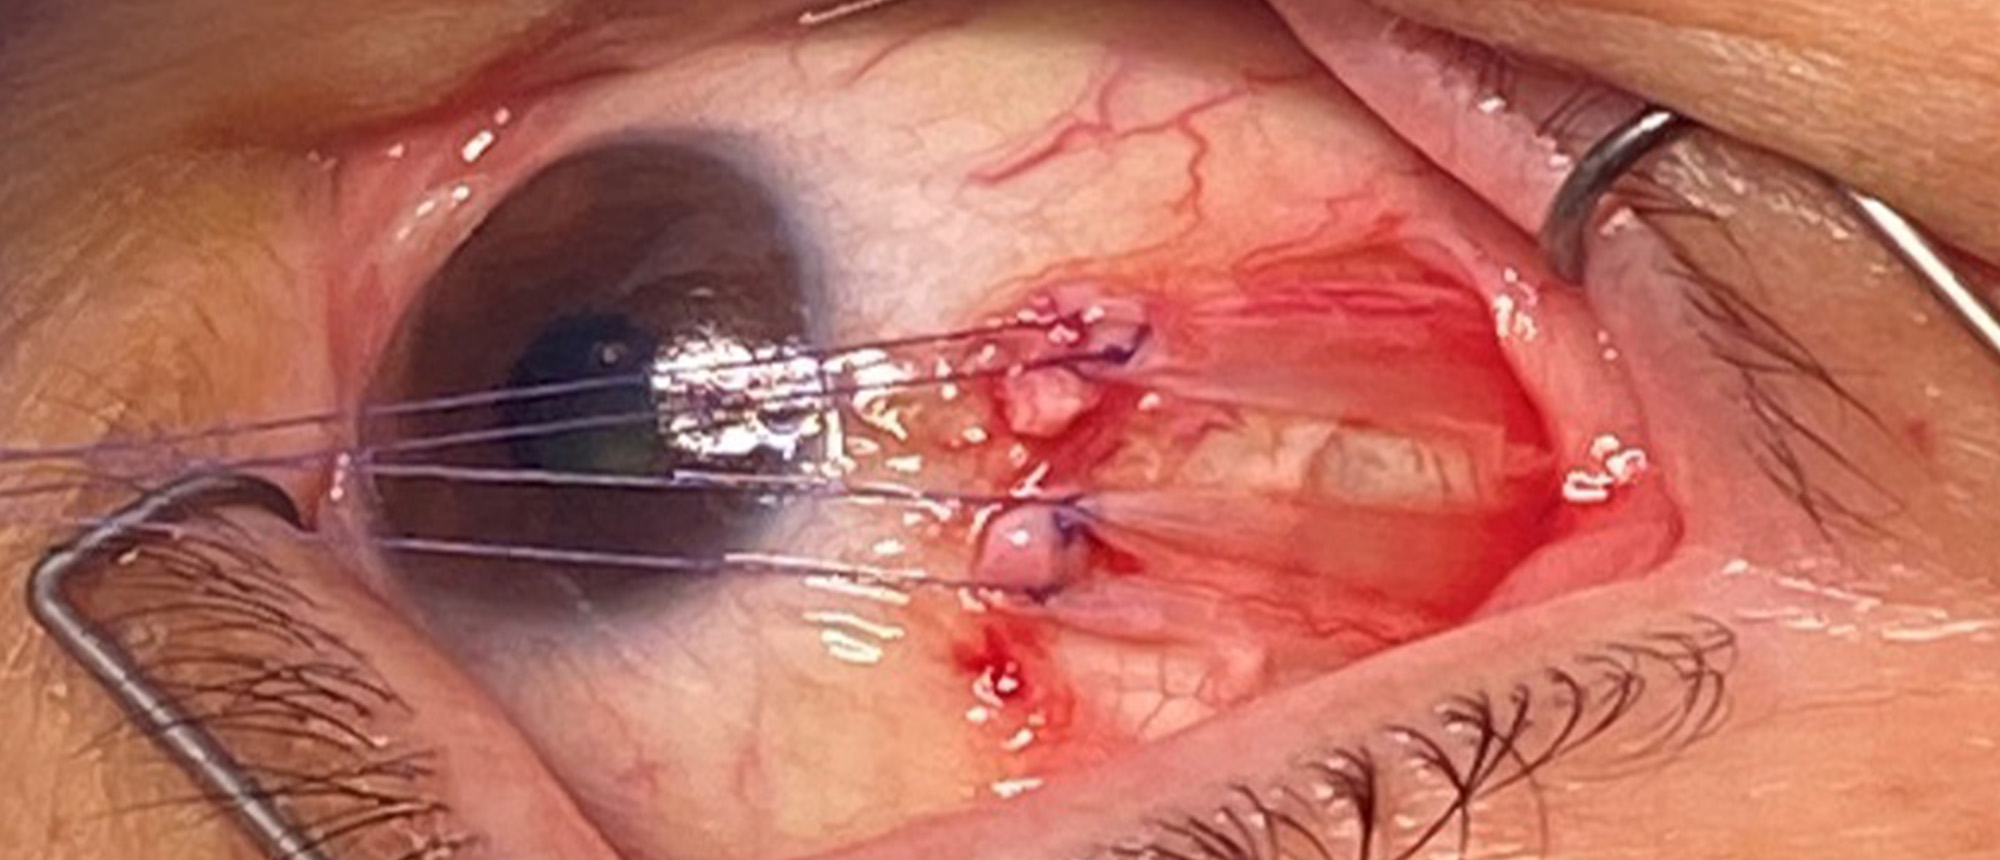

Superior Ophthalmic Vein Thrombosis with likely Cavernous Sinus Thrombosis A patient presented to the ophthalmology emergency room with a 1 day history of periorbital edema, decreased vision, pain with extraocular movements, and diplopia. Evaluation showed proptosis with significant injection and e…

This patient presented with a one day history of severe pain, reduced vision, diplopia, and proptosis. Imaging revealed a superior ophthalmic vein thrombosis. Extensive workup showed no definite underlying etiology. The patient was started on antibiotics, corticosteroids, and anticoagulation. There…